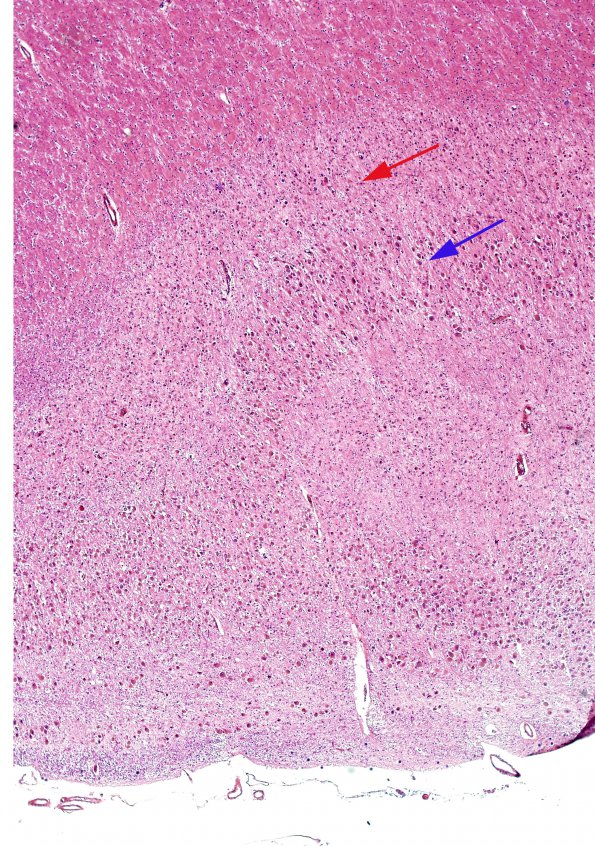

In this low magnification view of the LGN in this case, H&E stain demonstrates difference in size and numbers of neurons between layer 5 (blue arrow) and layer 6 (red arrow), which are innervated by different eyes and it is to be expected in a primarily unilateral involvement of one eye in this case.